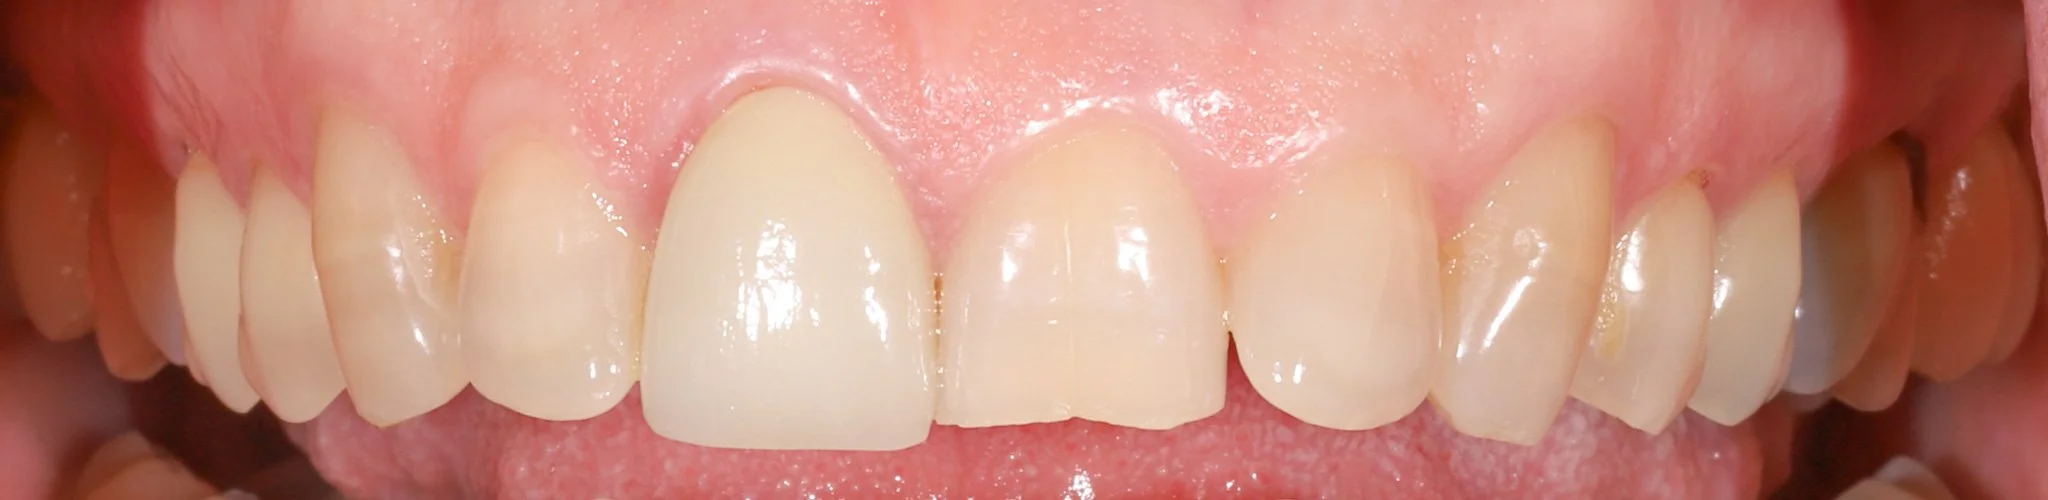

Teeth prior to restoring.  There are missing crowns, acid erosion, wear and decay.

Before: Missing crowns, acid wear

Teeth after restoring with bonded porcelain and gold, building back optimal aesthetics and function.

After: Proper fitting dentistry leads to healthy gum tissue